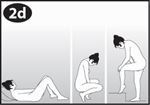

Waschen Sie sich vor dem Einsetzen oder Entfernen des Vaginalrings die Hände. Wählen Sie die Haltung, die Ihnen am bequemsten erscheint, z.B. Stehen mit einem angehobenen Bein, Hockstellung oder Liegen. Nehmen Sie NuvaRing aus dem Beutel. Halten Sie den Vaginalring zwischen Daumen und Zeigefinger, drücken Sie die gegenüberliegenden Seiten zusammen und schieben Sie den Vaginalring in die Vagina (siehe Abbildungen 1-4). Als Alternative können Sie wählen, ob Sie den NuvaRing Applikator als Hilfe zur Einführung des Vaginalrings verwenden möchten (siehe Bedienungsanleitung unten). Ist NuvaRing eingesetzt worden, sollten Sie ihn nicht spüren. Verspüren Sie ein unangenehmes Gefühl, ändern Sie vorsichtig die Position von NuvaRing (schieben Sie z.B. den Vaginalring etwas tiefer in die Vagina hinein), bis er bequem sitzt. Die genaue Position des Vaginalrings innerhalb der Vagina spielt keine Rolle.

Wählen Sie eine bequeme Haltung, um den Vaginalring einzusetzen. |

Wählen Sie für das Einführen des Vaginalrings die für Sie bequemste Haltung, wie liegend, hockend oder mit angewinkeltem Bein. |